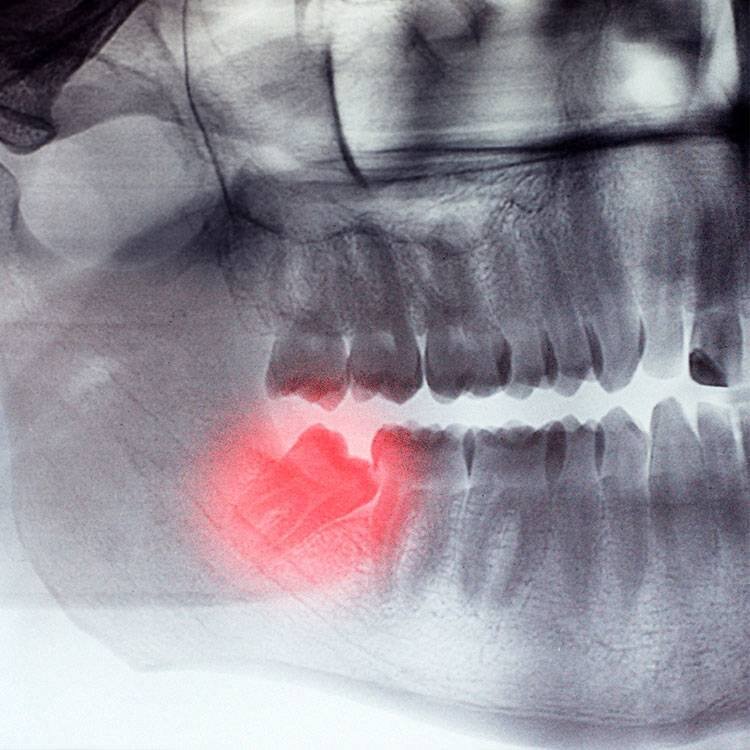

3. Бывает так что восьмёрка расположена под углом к семёрке, а это значит что полностью она возможно не прорежется. Но о чем можно с уверенностью сказать, так это о том что периодами, обычно в самые неподходящие моменты ( в отпуске/ перед важным мероприятием и тд) будет воспаляться десна вокруг пытающейся прорезаться восьмерки. Это явление называется перекоронит ,или воспаление капюшона, и сопровождается сильными болями, затрудненным глотанием, отёком и температурой🌡.